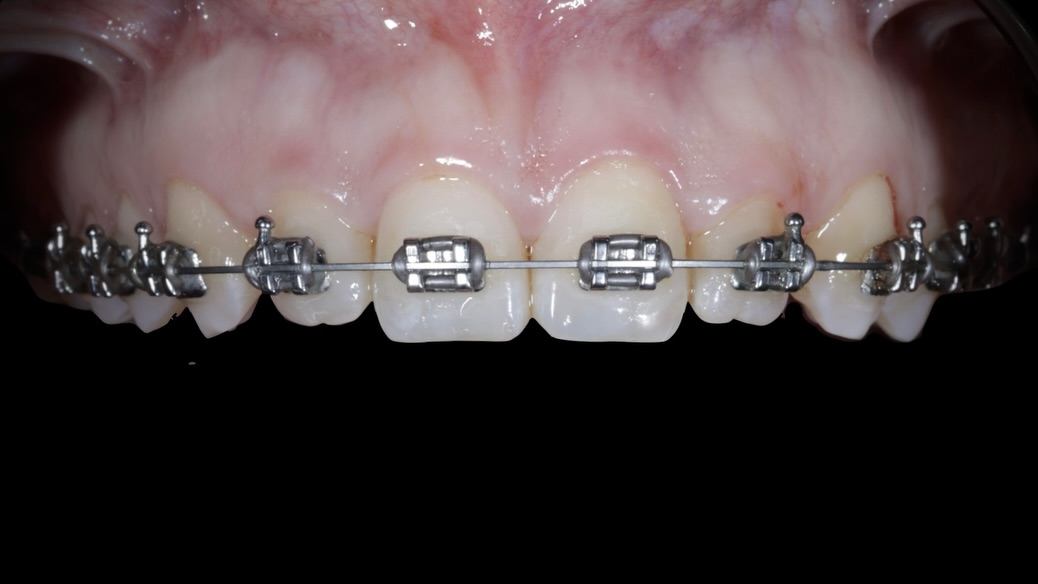

Se presenta un caso clínico de restauración directa en resina composite, ejemplo del valor de la precisión y la técnica meticulosa incluso en procedimientos considerados rutinarios dentro de la práctica diaria. El caso pone en evidencia la importancia del control de la morfología, la textura y la integración cromática, así como del adecuado aislamiento del campo operatorio y la estratificación del material, factores determinantes para conseguir un resultado natural, funcional y duradero. A través de una ejecución cuidadosa, se logró una restauración estéticamente imperceptible y funcionalmente estable, que respeta los principios de mínima invasión y adhesión efectiva. Este tipo de procedimientos, aunque cotidianos, reflejan la constancia y el nivel de exigencia clínica necesarios para ofrecer odontología de calidad en todos los casos, independientemente de su complejidad.